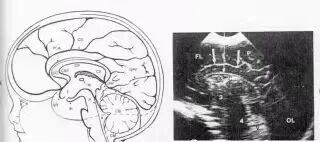

新生儿颅脑超声:是一项实用医疗诊断技术,与CT、MRI等成像技术构成互补关系,但它有着更强的实用价值,尤以无需患儿特殊准备、无创无辐射、便捷、重复性好,对早产儿的常规筛查、新生儿窒息、新生儿缺血缺氧性脑病、颅内出血、颅内感染、颅内占位性病变、脑积水、提高神经系统疾病,改善围产期脑损伤的预后等发挥了极大的促进作用。